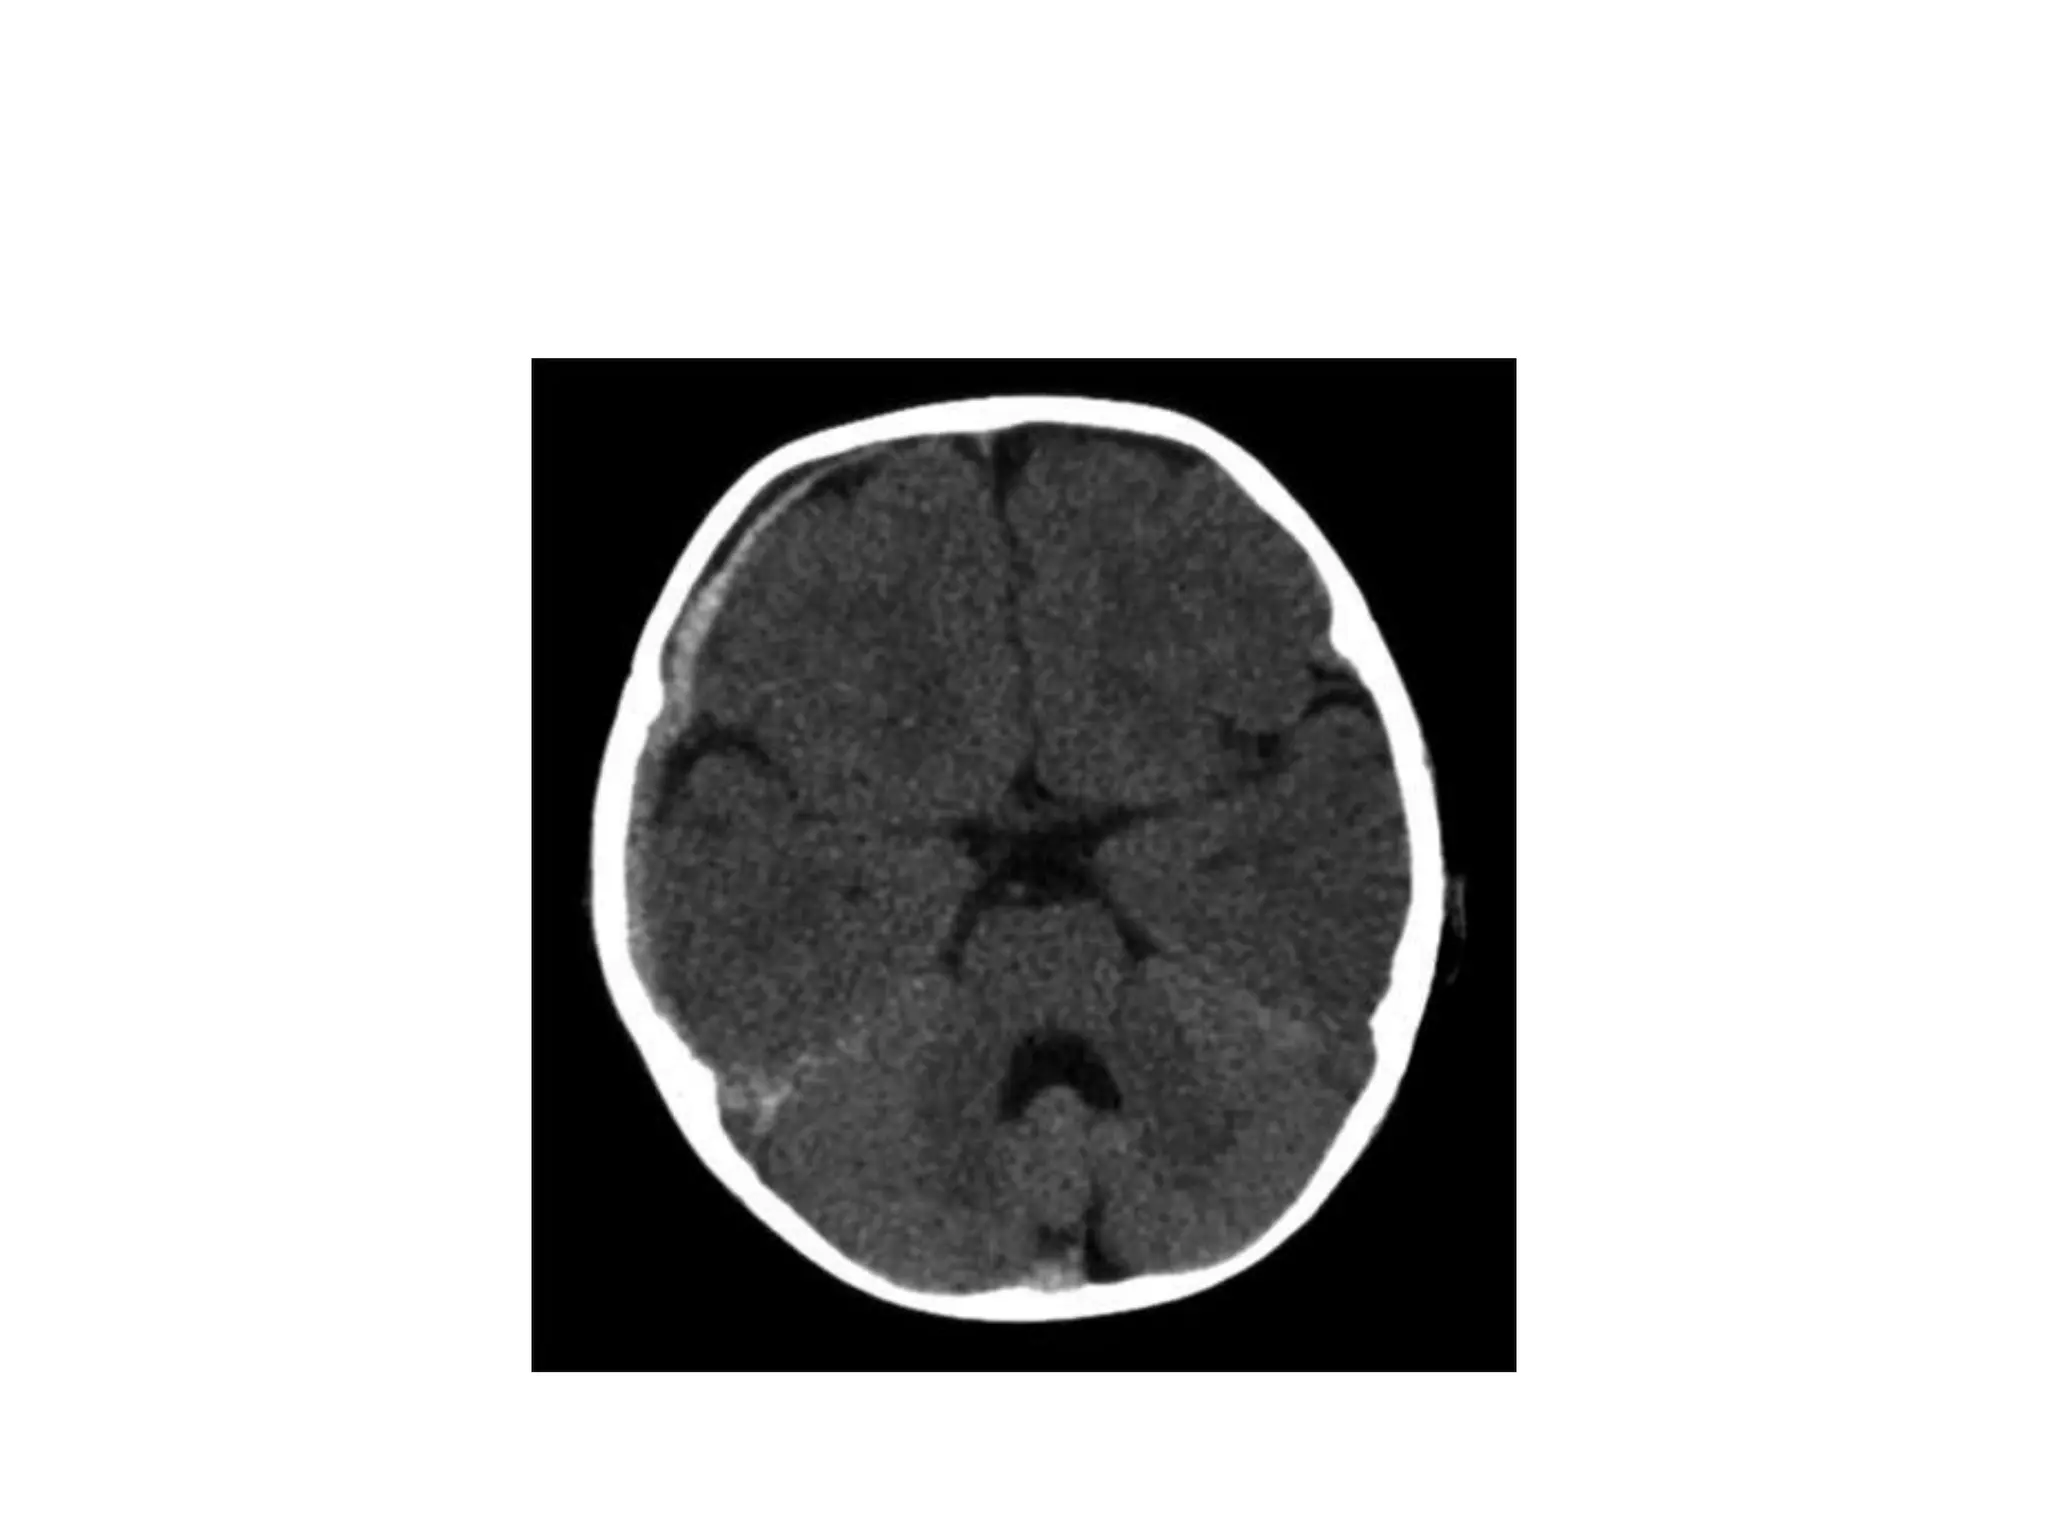

Normal CT scan

BrainGW interfaceIntraaxial and extra-axial lesionsGyri tight?

Blood Can Be Very BadVentricles – less ventricles = more problems